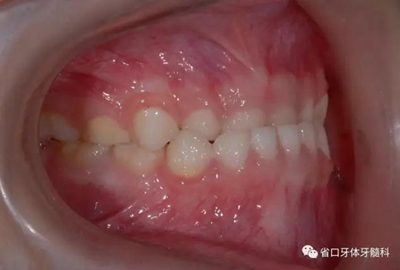

圖6 右側45度牙相

7.jpg